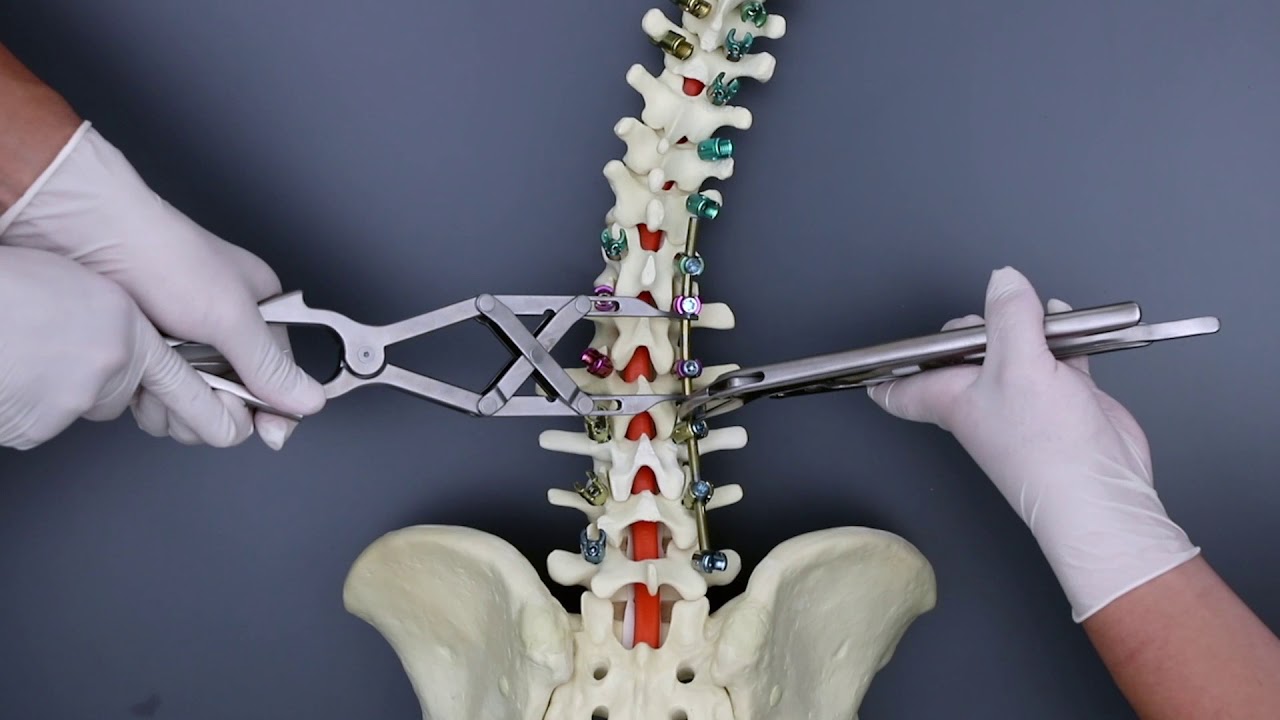

側 弯症側 手術側 ブログ側 ☆延長手術・・・☆側 -側 側わん症:VEPTRの会側 手術が必要な側弯症側 |側 ブログ側 |側 東京都品川の整体なら東京脊柱専門整体院側 側弯症対策!手術を避けるために日常で気をつけること側 |側 大阪市西淀川区佃の整体「なかむら鍼灸接骨院」千船駅徒歩4分側 側弯症コルセット側 術後側 手術が必要な側弯症5選側 -